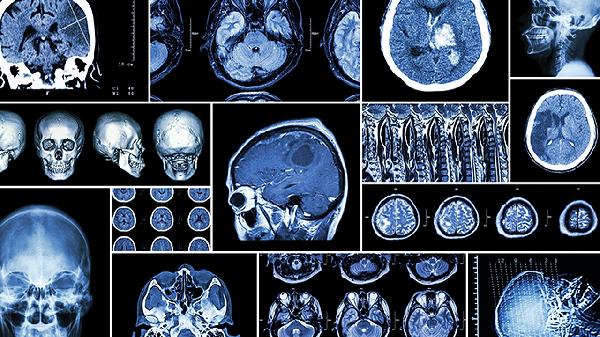

脑血栓可能由高血压、动脉粥样硬化、心房颤动、血液高凝状态、糖尿病等原因引起。脑血栓通常表现为肢体麻木、言语不清、头晕头痛等症状,需通过药物溶栓或手术取栓等方式治疗。